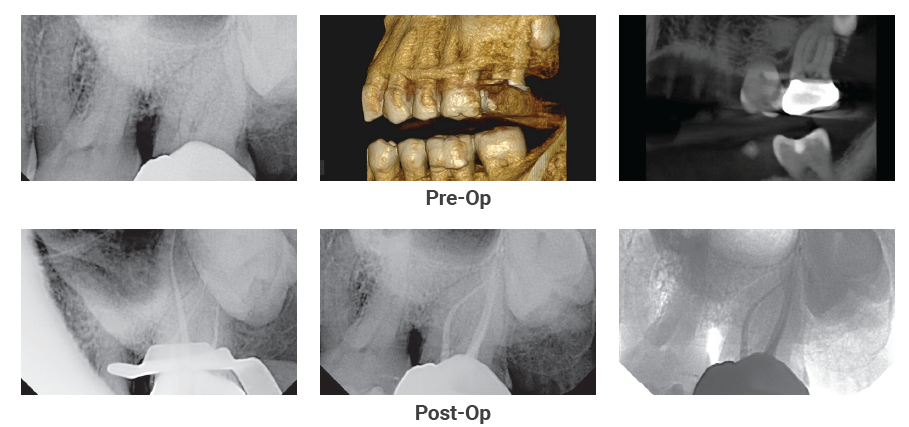

The patient came in with discomfort on tooth #19

The Case: The patient came in with discomfort on tooth #19. The diagnosis was a necrotic pulp with acute apical periodontitis…